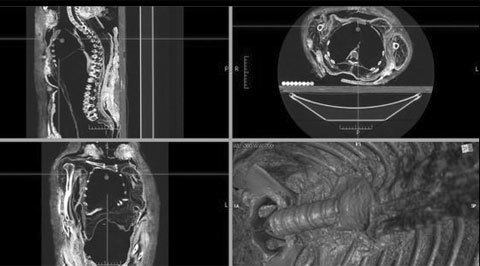

Kết quả chụp cắt lớp và tái dựng hình ảnh 3D cho thấy khoang bên trong cơ thể trống rỗng của xác ướp ROM910.5.3 ở Bảo tàng Hoàng gia Ontari, Canada. |

Để xác thực cách thức moi ruột xác ướp, nhà nghiên cứu Wade và cộng sự đã đọc tài liệu để tìm hiểu các chi tiết về cách thức tạo ra 150 xác ướp trong suốt hàng ngàn năng lịch sử của Ai Cập cổ. Họ cũng tiến hành chụp cắt lớp và tái dựng hình ảnh 3D của 7 xác ướp trong số đó.